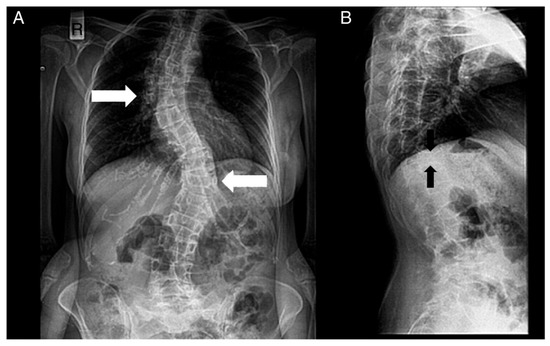

Figure 4. Radiographs of a patient’s spine. (A) Anteroposterior view. (B) Lateral view. The following are noted: scoliosis (double major—with a right thoracic and a left thoracolumbar curve—white noted: scoliosis (double major—with a right thoracic and a left thoracolumbar curve—white arrows), and biconcave deformities of the upper and lower endplate (fishbone deformity—black arrows) of many vertebrae and decreased bone density.

Figura 4. Radiografías de la columna de un paciente. ( A ) Vista anteroposterior. ( B ) Vista lateral. Se notan los siguientes: escoliosis (doble mayor — con una curva torácica derecha y toracolumbar izquierda — flechas blancas) y deformidades bicóncavas de la placa terminal superior e inferior (deformidad en espina de pescado — flechas negras) de muchas vértebras y disminución de la densidad ósea.The diagnosis of HCS is suspected via the observation of physical appearance and radiological findings, but the final diagnosis is reached via genetic sequencing of exon 34 of NOTCH2.